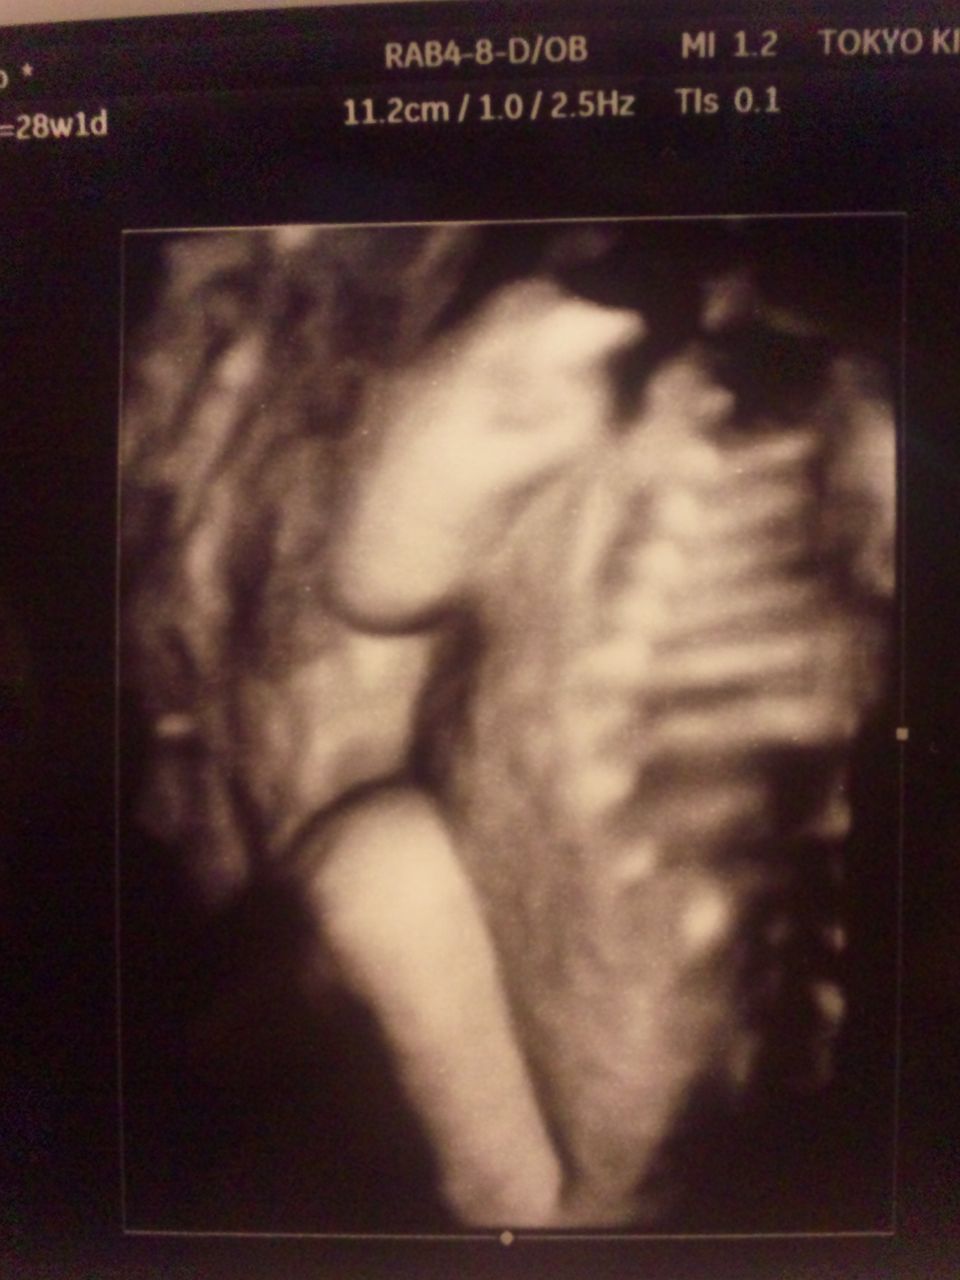

をを、これは噂の3Dエコーってやつですね!

スキャン位置によっては皮膚がレンダリングされず骨が出て凄い画像になりますがw

あいにく、中の人は恥ずかしがりやさんのようで背中を向けてまして、顔がどうなってるかはわかりませんでした。

斜め後ろからの顔のラインはちぃ太郎そっくりです。